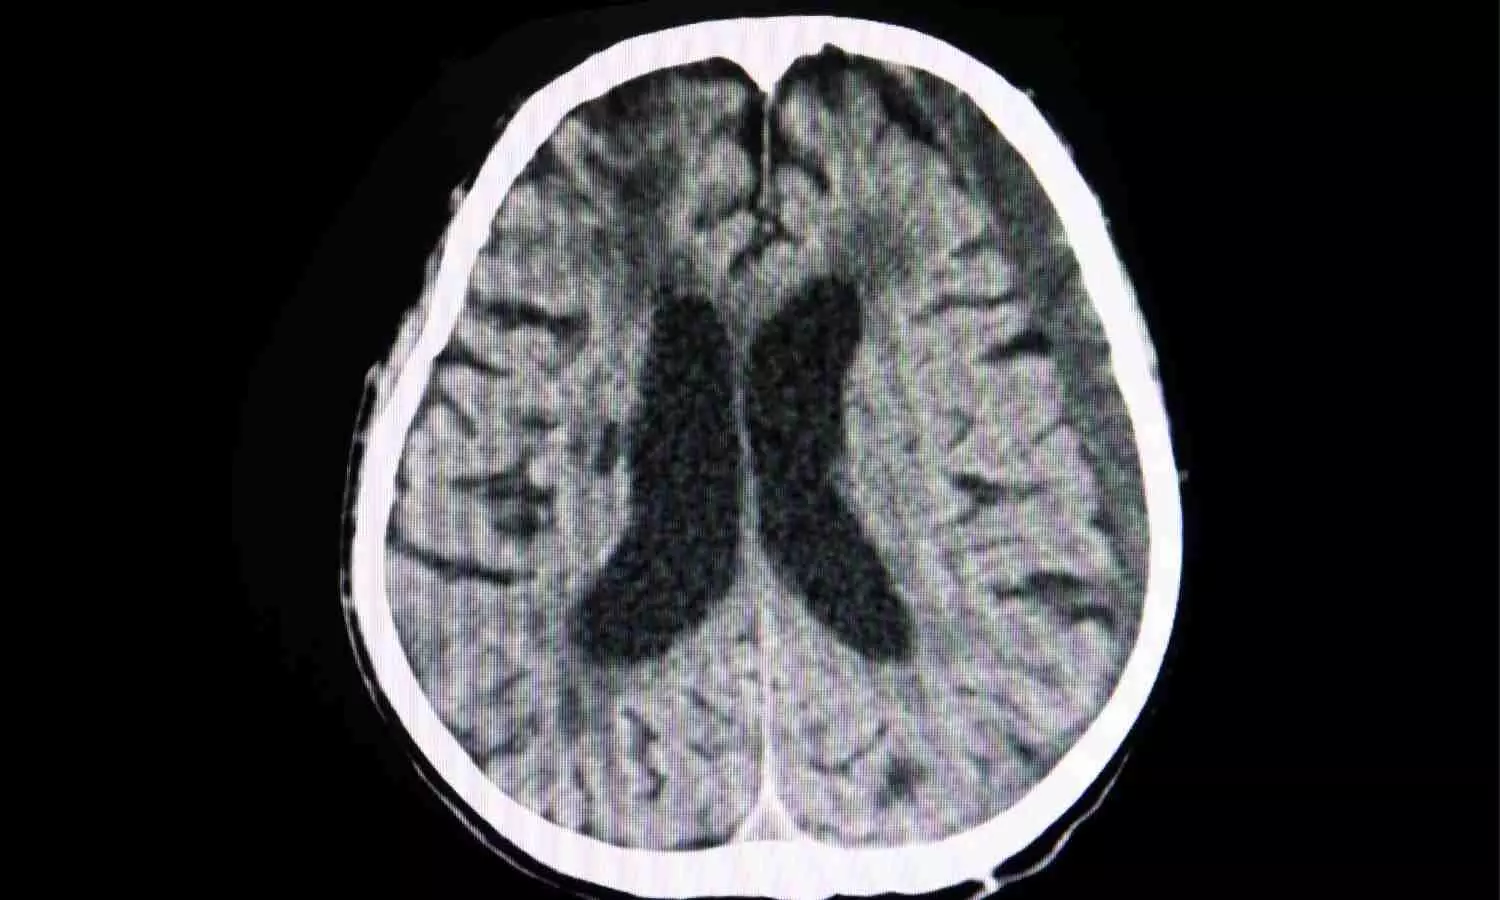

Study Finds No Clear Benefit of Early Surgery Over Conservative Care in Traumatic Acute Subdural Hematoma